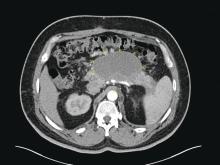

Large pancreatic fluid collection (star) causing gastric compression (stomach outline marked with arrows) and biliary obstruction (arrowheads).

Patients with AP frequently develop peripancreatic fluid collections (PFCs). Based on the revised Atlanta classification, those are categorized into four types (Table 2, Figures 1-4).

It is only the mature PFCs, which are symptomatic resulting in abdominal pain, nausea, early satiety, gastric outlet obstruction, failure to thrive, and/or biliary obstruction, that need to be drained/debrided42. Minimally invasive approaches have shown to result in better outcomes when compared to open laparotomy. Minimally invasive approaches include placement of percutaneous drainage catheters by interventional radiology (retroperitoneal approach preferred when feasible), endoscopic drainage/debridement, laparoscopy, and retroperitoneal necrosectomy following a step-up approach43.

While surgery is still an option for patients with symptomatic mature PFCs, endoscopic ultrasound-guided drainage in expert hands has been shown to be cost effective, with shorter hospital stay and even decreased risk of cyst recurrence compared with surgical cyst-gastrostomy creation44. Ultrasound or computed tomography-guided drainage of such collections with a percutaneous catheter is an equally efficacious option when compared to the endoscopic approach. However, patients undergoing endotherapy require fewer procedures and imaging studies and shorter length of stay45 when compared with radiological interventions.